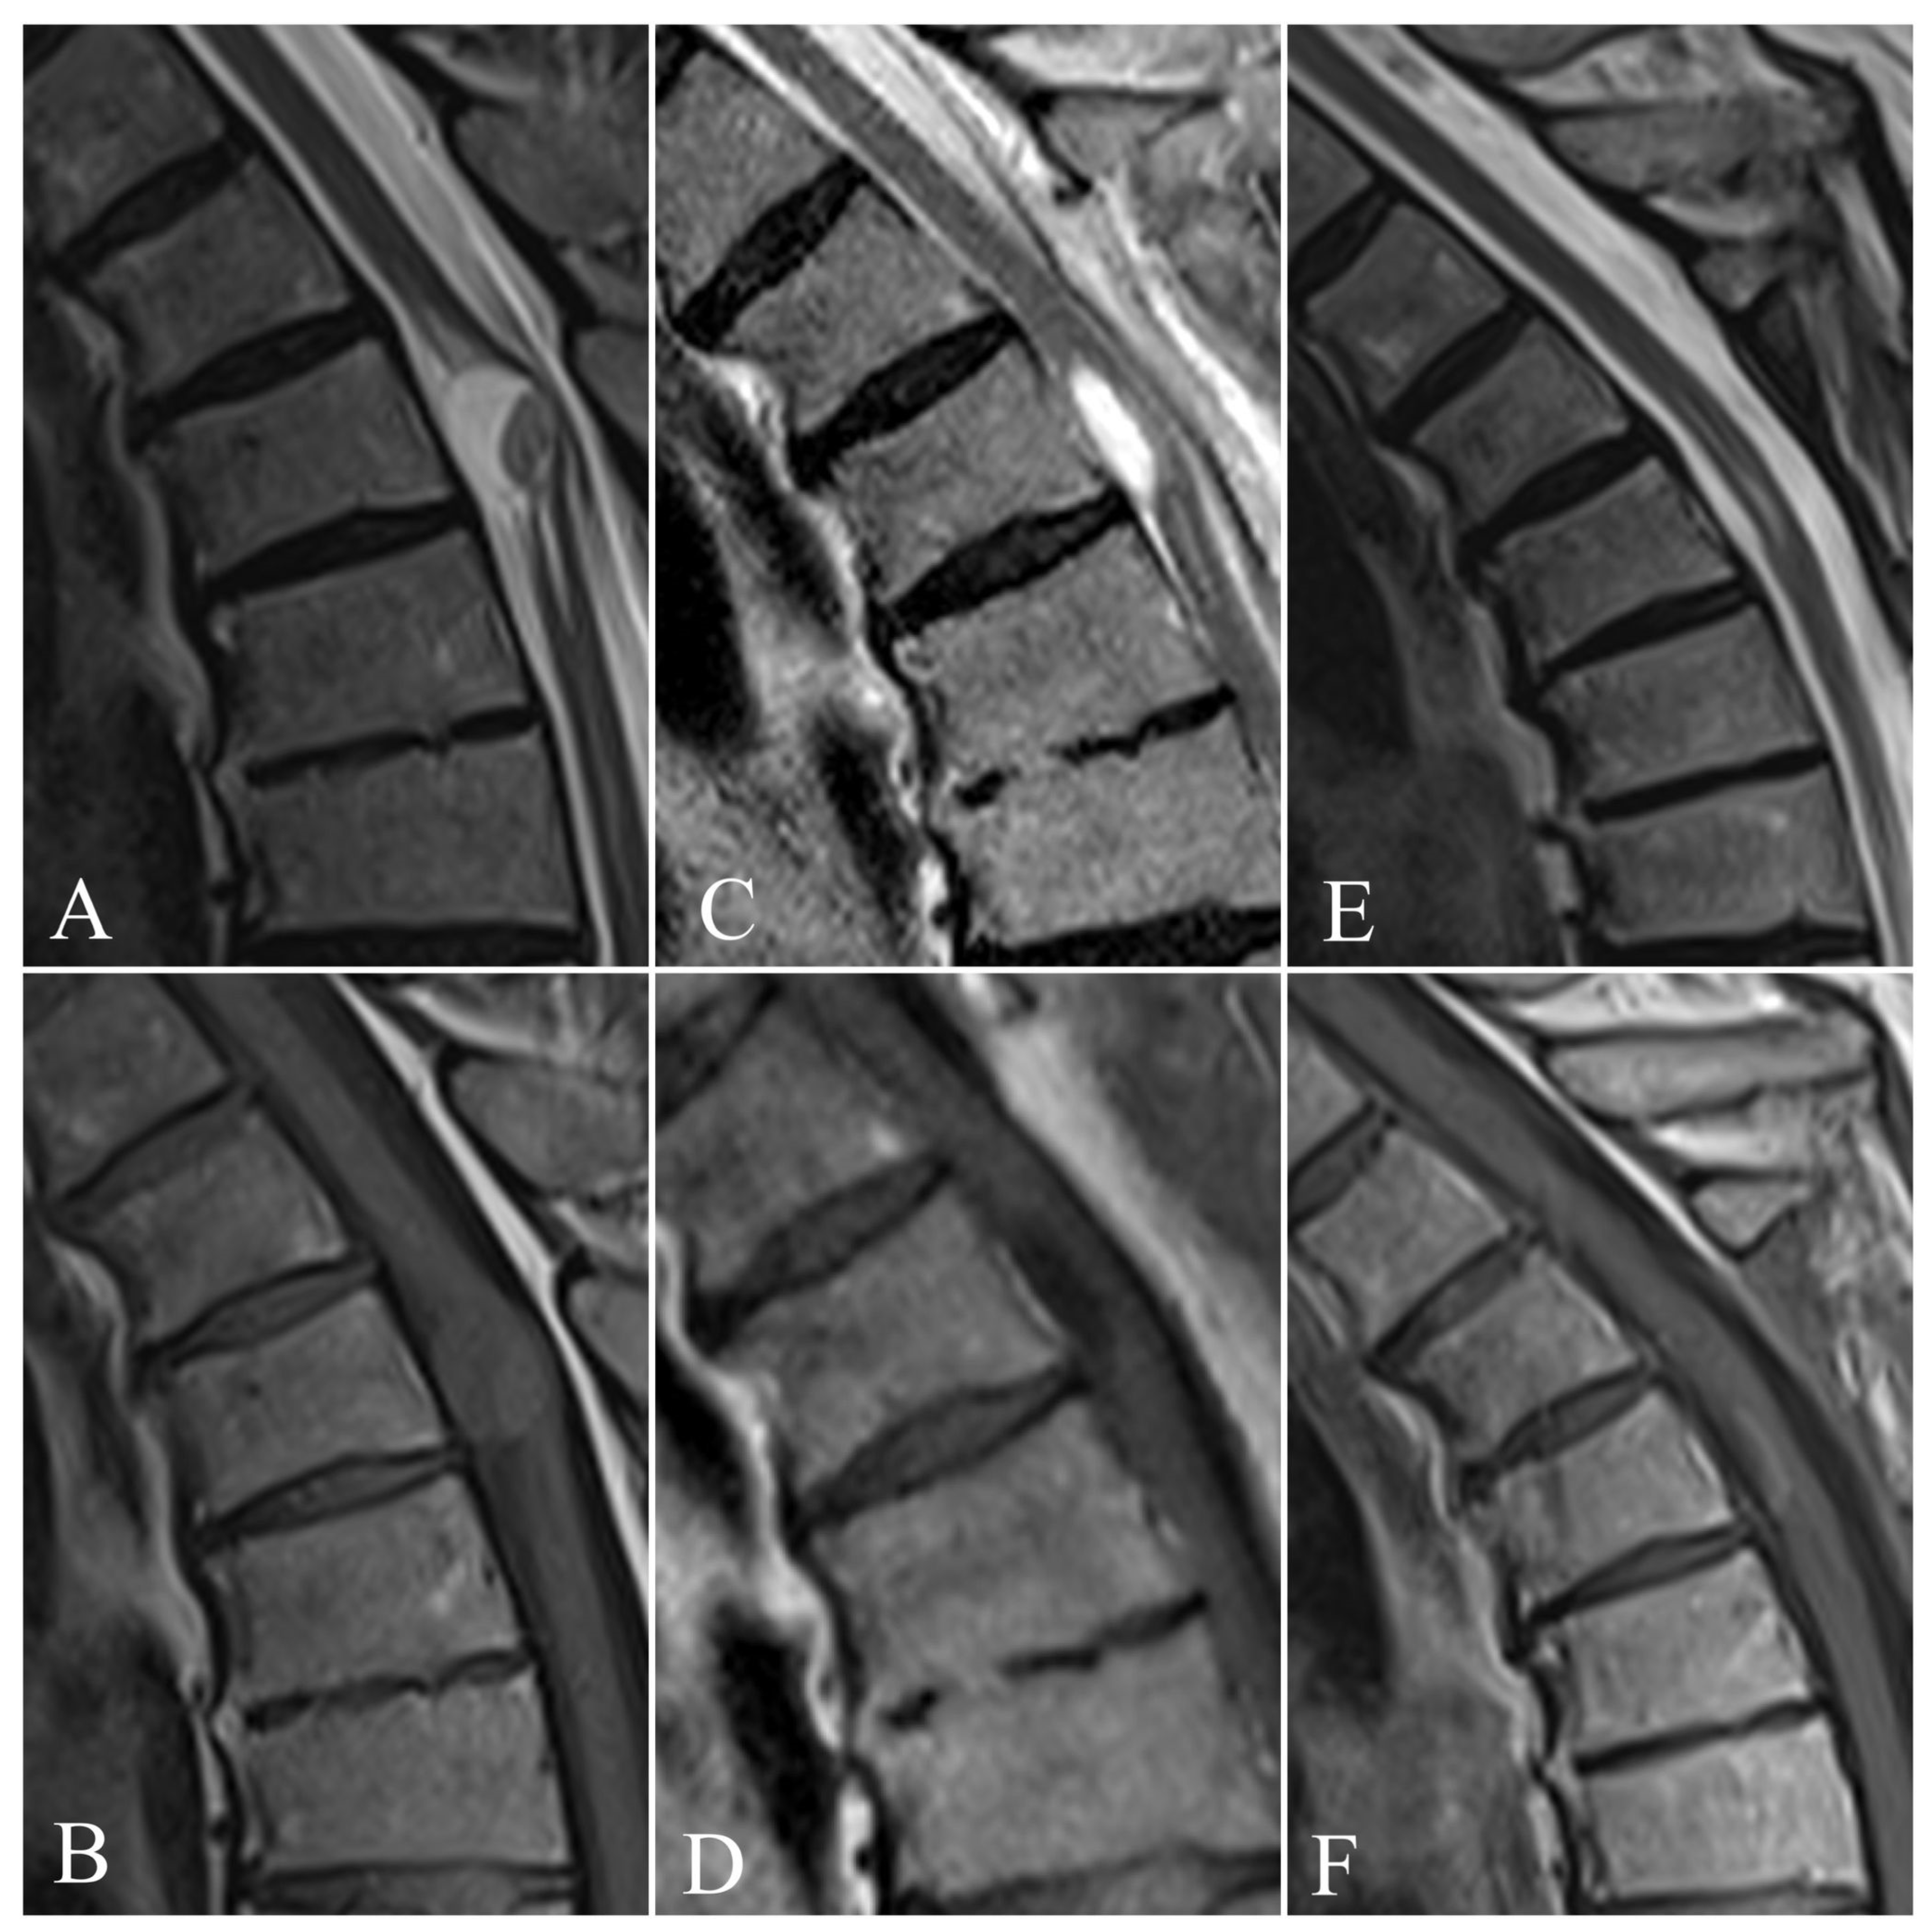

| MRI (n = 50) |

| Segmental widening and swelling of spinal cord |

| Ring-enhancing margin (abscess) |

| Cystic lesion with ring enhancement |

| CSF flow obstruction |